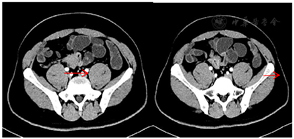

患者于2016年4月于复旦大学附属中山医院骨科门诊首诊,行下肢X线、CT检查,提示:有T12-L1椎间盘突出,T12-L1后缘增生伴后凸,右侧小腿单纯肌肉萎缩,予神经营养药物治疗,随访观察。2016年7月骨科门诊复查,症状无改善,双下肢MRI检查,提示右小腿内后侧肌群水肿改变,炎性病变可能大。风湿科会诊查风湿抗体谱,除抗SSA抗体为阳性外其余均阴性。4个月后于骨科复诊完善腰椎MRI,提示T12-L1椎间盘突出(压迫硬脊膜囊)(图1A、B)。2016年9月入院复查风湿科全套检查及小腿MRI,提示:双侧腓肠肌及比目鱼肌病变伴右侧小腿肌肉萎缩(免疫性病变可能,建议局部穿刺活检);表现:右侧腓肠肌及比目鱼肌内T2WI高信号小斑片较前减少,左侧较前增多(2016年7月15日)。心电图、胸片、血常规、出凝血、肝肾功能均无殊。肌酸激酶281 U/L,肌酸激酶MM亚型259 U/L,乳酸脱氢酶299 U/L,尿素11 mmol/L。

术后下床活动术区及右髋关节略有疼痛,予以对症处理后疼痛改善,右小腿酸胀不适感减轻。术后腰椎正侧位X光片,提示:未见骨质异常,T12-L1椎间隙稍狭窄。术后1个月行胸腰椎三维重建,提示:腰椎生理曲度近变直,T12-L1椎间盘突出,L4-5椎间盘轻度膨出,较术前有所好转(图1F、G)。